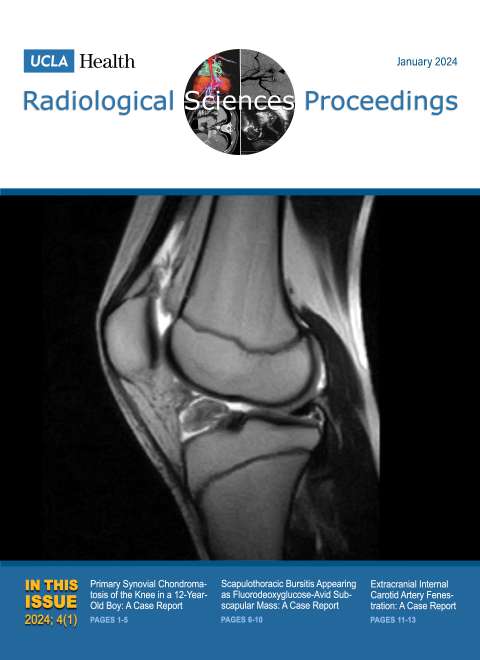

January 2024

Volume 4, Issue 1

- Primary Synovial Chondromatosis of the Knee in a 12-Year-Old Boy: A Case Report

- Scapulothoracic Bursitis Appearing as Fluorodeoxyglucose-Avid Subscapular Mass: A Case Report

- Extracranial Internal Carotid Artery Fenestration: A Case Report